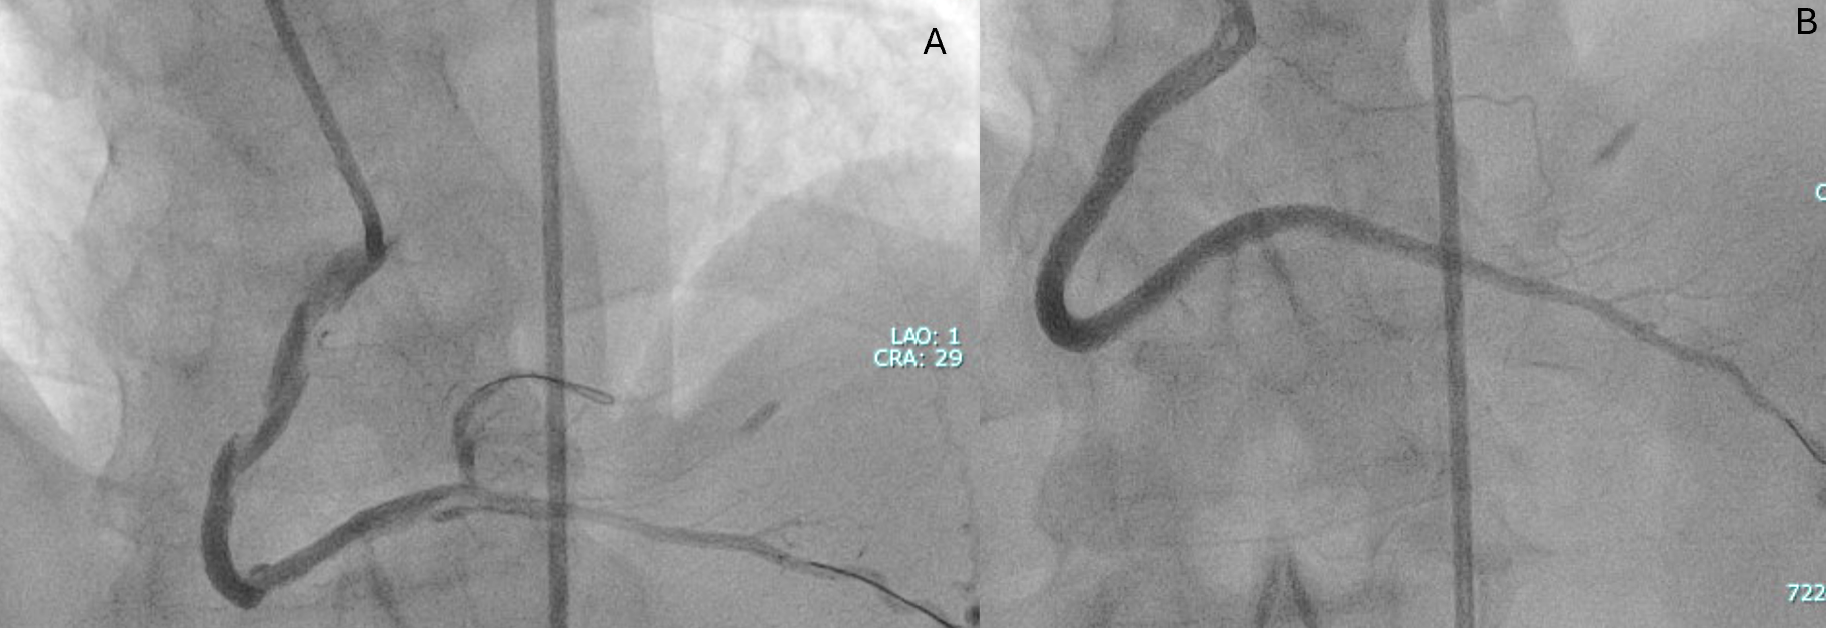

A primary retrograde strategy was selected but septal collateral wiring was unsuccessful. Epicardial collaterals from the LAD were subsequently crossed (Figure 2, Video 2); however, a retrograde wire (Confianza Pro 12; ASAHI INTECC) failed to puncture the distal cap. Antegrade wire (Gladius MG; ASAHI INTEC) knuckle was used until just before it reached the distal cap (Figure 3, Videos 3 and 4). A 3.0 x 20-mm TREK balloon (Abbott) was delivered retrogradely through the epicardial collateral and inflated at the bifurcation (Video 5). Next, an antegrade wire (Gladius EX; ASAHI INTECC) was delivered into the distal true lumen of the posterior descending artery (Figure 4, Video 6). The RCA was successfully stented with an XIENCE Pro drug-eluting stent (Abbott), with restoration of Thrombolysis in Myocardial Infarction 3 flow (Figure 5, Video 7).